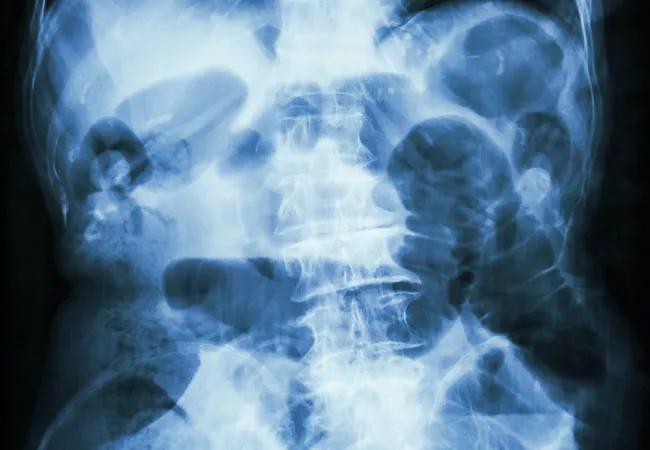

Early small bowel obstruction (SBO), defined as an obstruction that occurs within the first 30 days following surgery, is a rare complication of hysterectomy for benign indications, according to a new study. The condition is associated with variables such as wound class, uterine size and perioperative transfusion.

Early SBO warrants special attention. It can be difficult to distinguish between mechanical and nonmechanical obstruction during this period, as the obstruction may be due to adhesions or paralytic ileus.

Early SBO occurred at a rate of 5.9 per 1,000 hysterectomies for the cohort of approximately 48,000 patients who underwent hysterectomies from 2014-2016. Dr. Dassel notes, “The low incidence of SBO after hysterectomy is useful to know in order to further educate patient on the risks associated with hysterectomy.”

Patients who developed SBO were more likely to be nonwhite, have a prior history of abdominal or pelvic surgery, to smoke and to have preoperative comorbidities including hypertension and dyspnea. “The association of SBO with hypertension and dyspnea is surprising, though may be related to confounders such as age,” says Dr. Dassel. Additional risk factors for SBO include contaminated wounds, perioperative transfusion, operative time greater than 170 minutes, uterine weight over 250 grams, lysis of adhesions and concomitant appendectomy.

“Furthermore,” Dr. Dassel states, “anything that increases inflammation and thereby scar tissue and adhesions in the pelvis is not surprisingly associated with SBO. The association with lysis of adhesions may have to do with the patient’s innate risk of developing adhesions, or because there is some other sort of inflammatory process at work in the pelvis.”

In most patients, SBO develops after discharge and can be managed conservatively and without surgery. In the study cohort, there were 123 readmissions, mainly for the management of SBO. Intestinal obstruction was the primary admitting diagnosis for the majority of these patients. Presenting symptoms may include severe bloating, abdominal pain, nausea and constipation.

Only 23% of patients who developed early SBO underwent a second surgery in the 30-day post-operative period. Of these 66 patients undergoing a second surgery, approximately 88% underwent reoperation for SBO management.